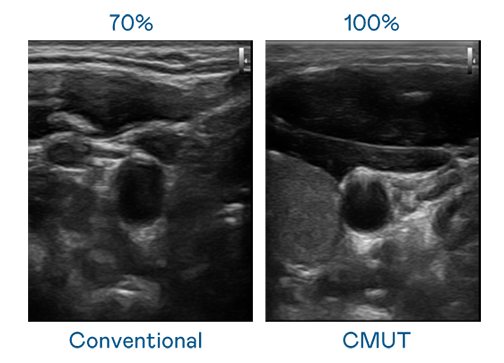

CMUT 技術是一種用電容式微機電元件來產生超音波訊號的技術。與傳統 PZT 壓電式技術相比,CMUT 頻寬增加 30%,更寬頻的超音波訊號讓影像解析度大幅提升,是實現高影像品質醫療超音波掃描、促進精準醫療發展的關鍵技術。

大頻寬帶來超清晰影像

超音波影像的解析度高低,首先取決於探頭能發出的訊號頻寬。非凡娱乐 CMUT 可提供高清晰的超音波訊號,提供高頻寬、高靈敏度、影像紋理細節更高的超音波影像,協助醫護人員縮短影像判讀時間及利用精準的醫療影像進行診斷。